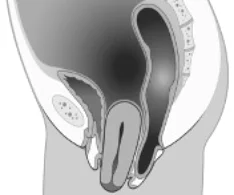

Cystokéla

Prolaps uteru

Rektokéla